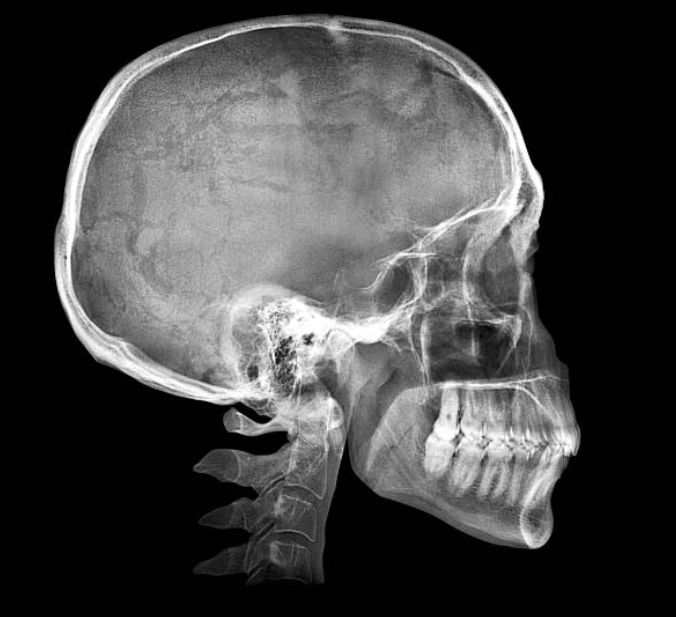

Image 4: Adenoid face with a slightly angled malocclusional plane caused by natural backwards and downwards rotation of the mandible/maxilla due to inactivity of the masticators. Impacts airways. Notice the head is tipped upwards (relative to image 2 especially) to artificially open the airways. Subject has poor but necessary posture.

Image 5: Normal face with a horizontal malocclusional plane. This is what you guys know as "forward growth," but is really just optimal development of the masticators preventing backwards and downwards rotation of the mandible. Does not impact airways. One of the best health indicators of all time.

Xray

REAL LIFE:

Optimal: